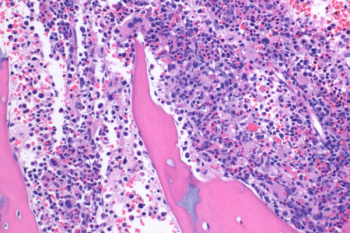

A previously healthy 5-week-old former term newborn male presented to the emergency department with the chief complaint of fever ranging from 101-104°F for 2 days. He also had been fussy and not been eating well. The infant remained febrile despite his mother’s administration of Infant Tylenol every 4 hours at home. His mother denied any cough, rhinorrhea, bleeding or bruising, diarrhea, vomiting, and reported stool and urine had been normal. What's the diagnosis?